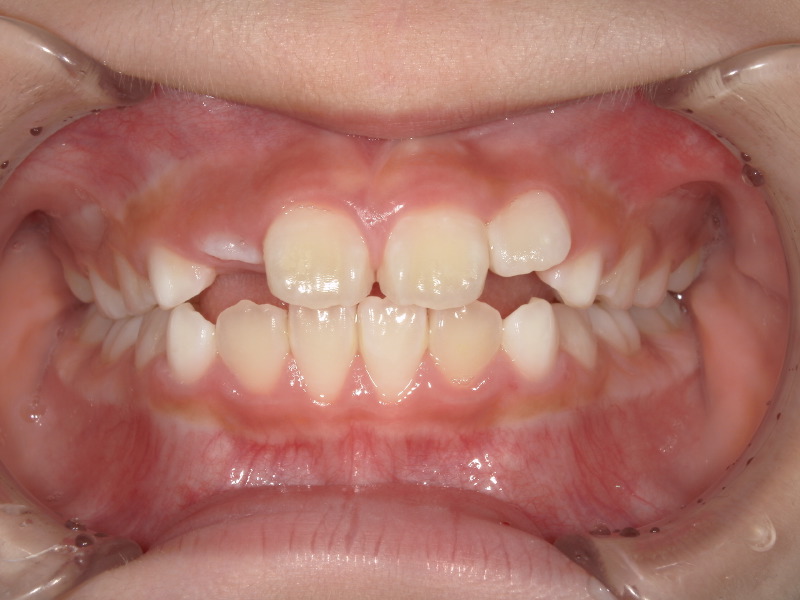

アクティビティーやマウスピースを継続してくれており卒業も近かったのですが、まだお口が家で開いていることもあり卒業まで少し苦戦していました。

卒業後

アクティビティーの卒業

プログラムで行うアクティビティーが終わった後は癖の改善があるかなども確認します。

そこでアクティビティーを卒業するかを診断します。

卒業になっても生え変わりの間は数ヶ月に一度来院してもらいます。

年齢にもよりますが卒業後に装置を併用してつけることもあります。

最終的には綺麗な噛み合わせになり、初めよりも上と下の真ん中の位置関係もよくなっています。